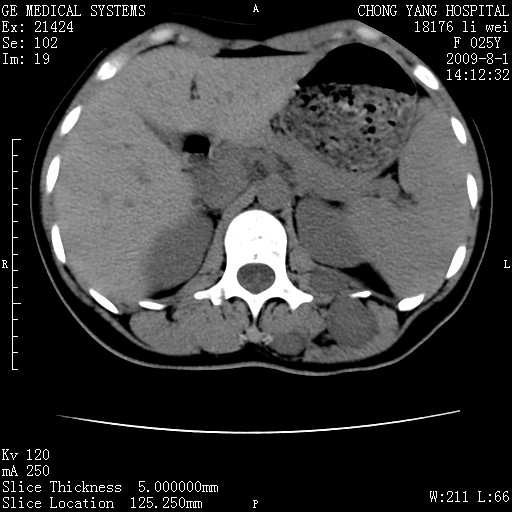

以下是引用拾荒者在2009-12-30 21:45:00的发言:[br]ct21383:神经纤维瘤病( nf) [br] [br] 神经纤维瘤病。四肢都有,影响美观,四肢上的手术了。[br] [br] [br]谢谢!